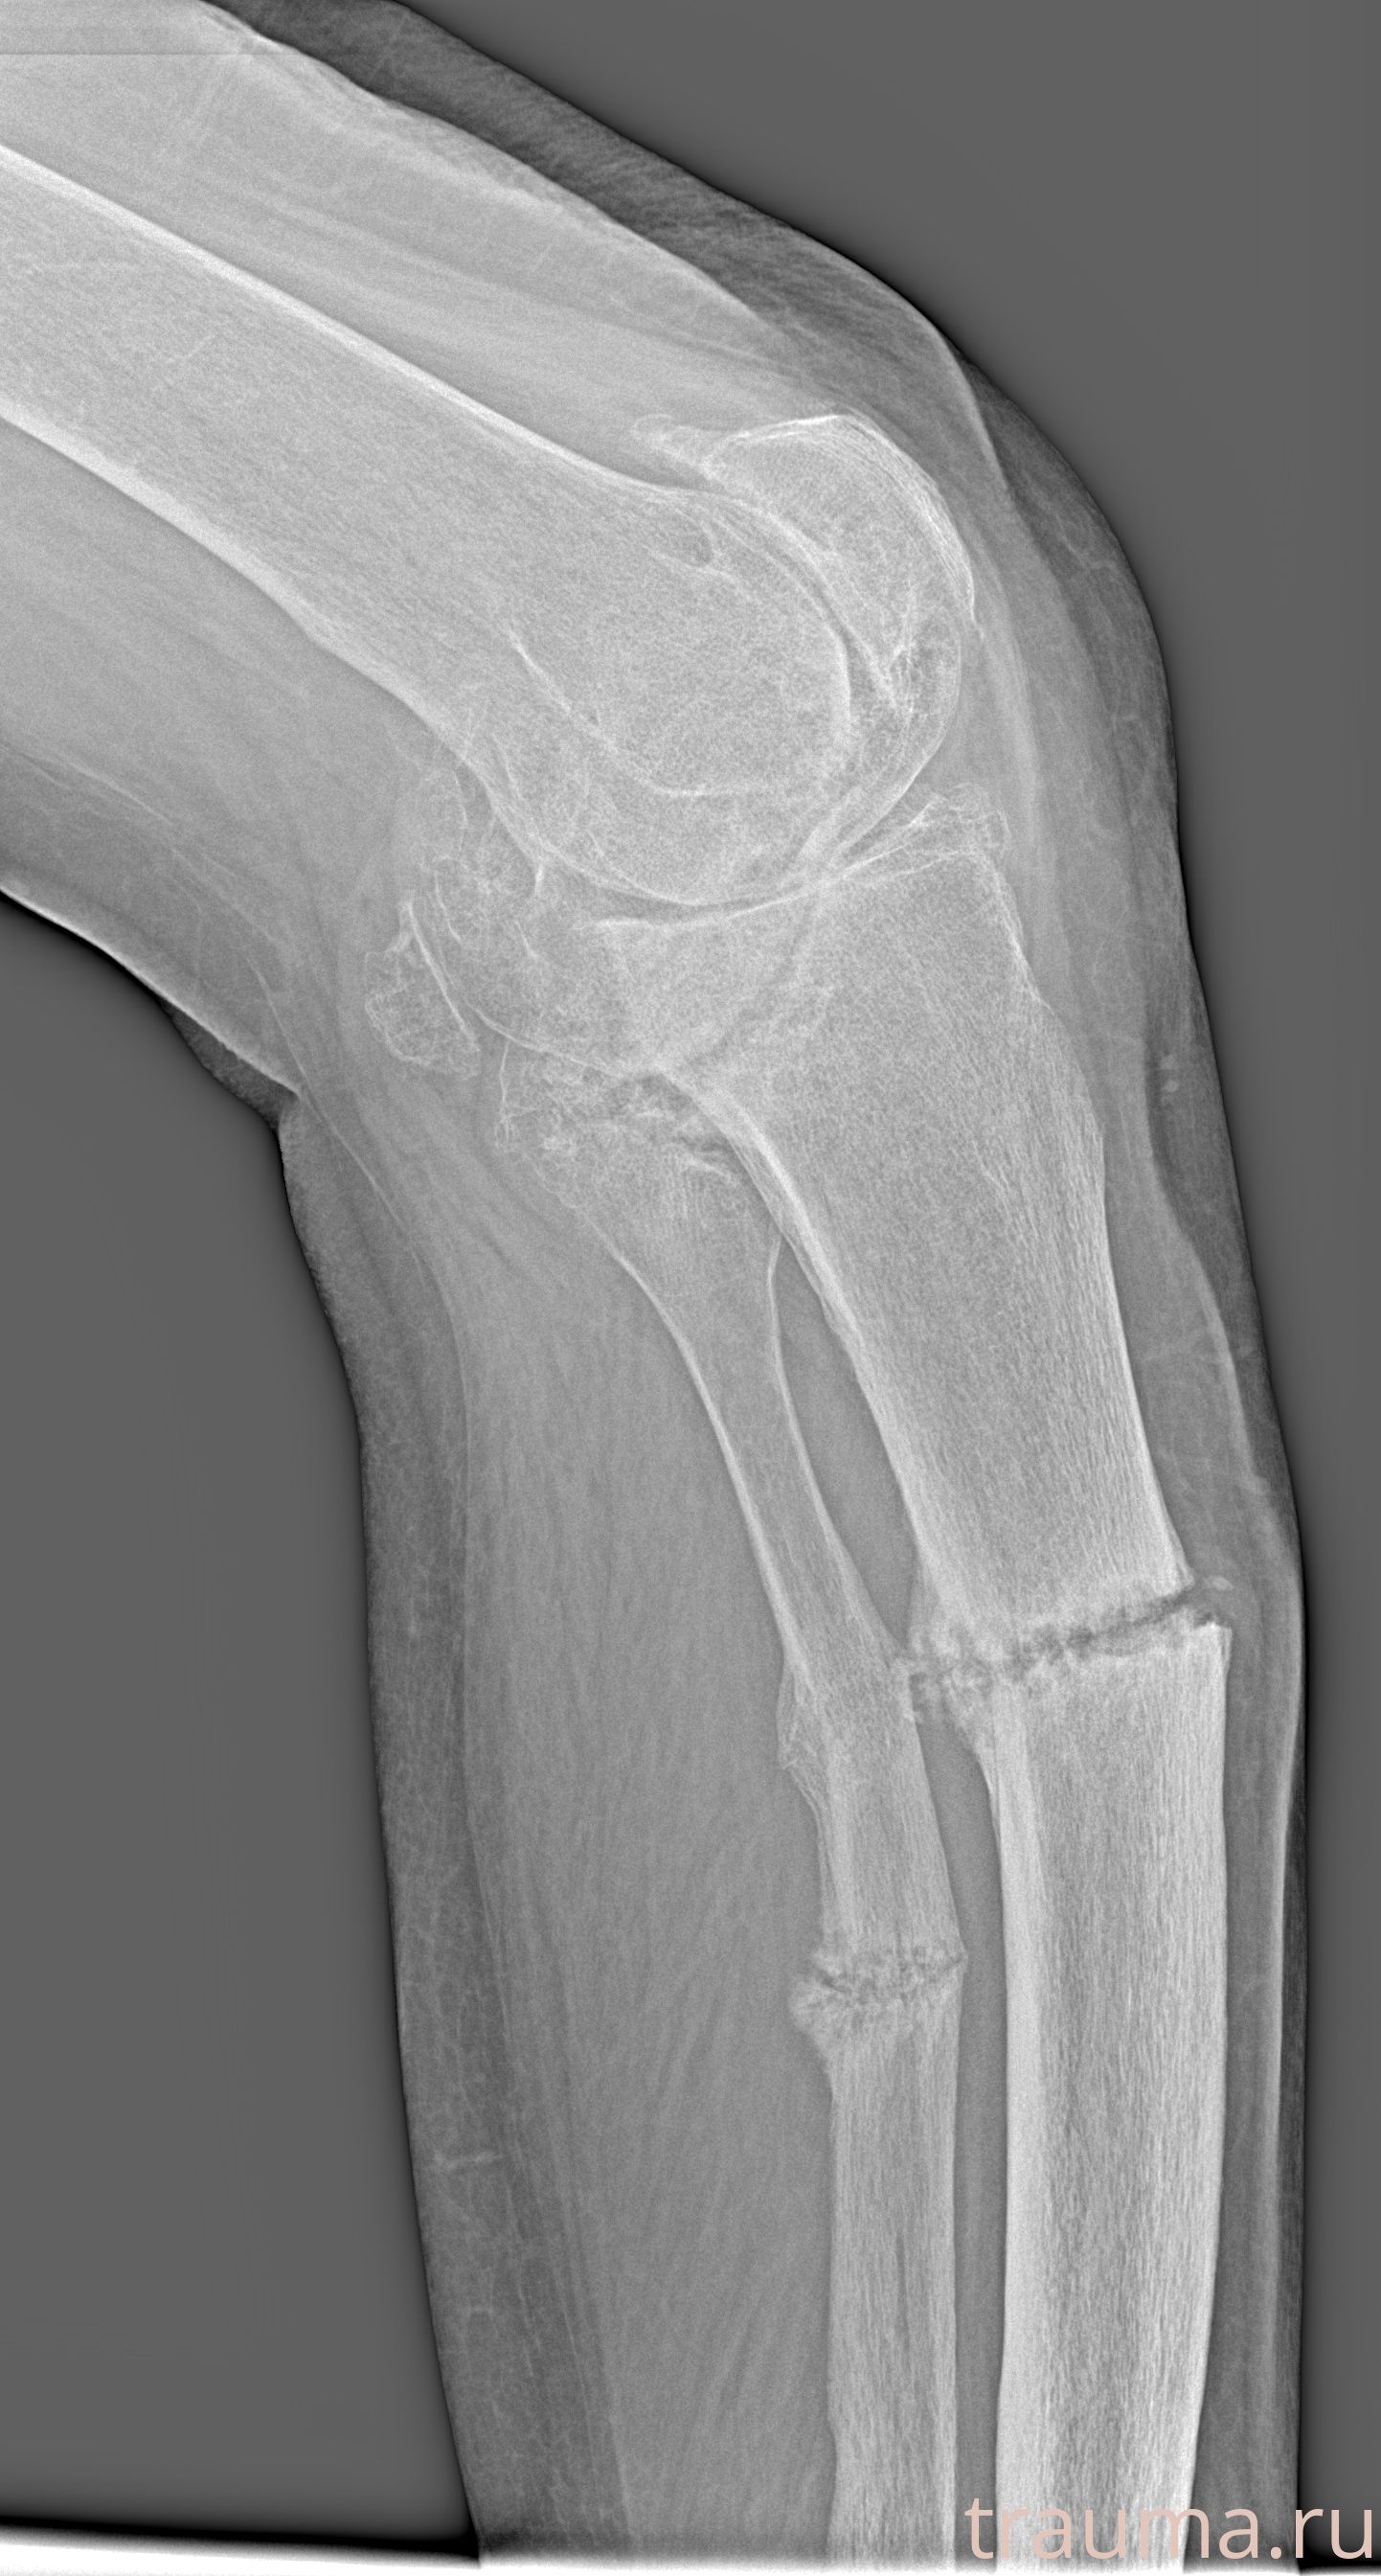

Рентгенограммы

Рентген на дому: по вашему адресу приезжает врач-рентгенолог, травматолог-ортопед с мобильным рентгеновским аппаратом, проводит диагностику травмы или заболевания, делает необходимые рентгенограммы, дает рекомендации по дальнейшему лечению. Получить качественные снимки в домашних условиях возможно благодаря уникальной методике, разработанной МосРентген Центром для института  Склифосовского